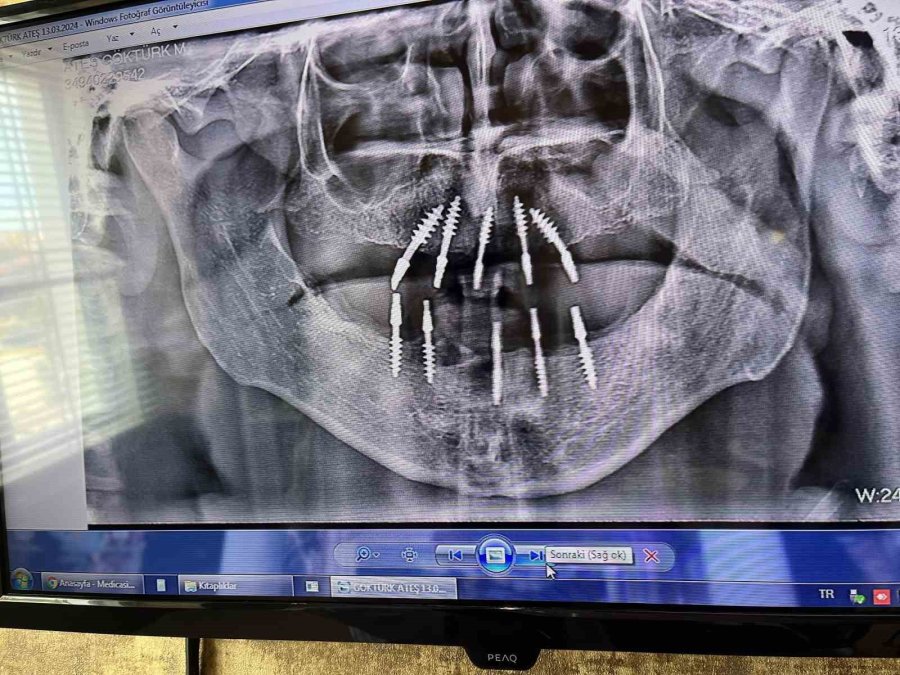

Fizyomer Terapia Estetica Denta Fizik Tedavi ve Rehabilitasyon Tıp Merkezi Diş Hekimi Mutlu Turgut, uygulanmaya başlanan ve normal implanta göre daha çabuk kullanıma hazır olan protezlere imkân sağlayan monoblok implant sistemi hakkında bilgi verdi. Monoblok implantta operasyondan 3 gün sonra protezlerin ağza yerleştirildiğini söyleyen diş hekimi Turgut, klasik implant sisteminden ayıran en önemli farkın hızlı uygulama olduğuna değindi. 150 tane Monoblok implant uyguladıklarını söyleyen Diş Hekimi Mutlu Turgut, geri dönüşlerin iyi olduğunun altını çizdi.

Monoblok implant sistemi hakkında konuşan Fizyomer Terapia Estetica Denta Fizik Tedavi ve Rehabilitasyon Tıp Merkezi Diş Hekimi Mutlu Turgut, "Monoblok implant dediğimiz sistemde klasik implanta göre avantajımız, cerrahi fazında daha az invaziv işlem yapılmasıdır. Yani punch tekniğiyle sadece diş eti üzerinde, implant yerleştirecek bölgede 2-3 milimetre çapında bir diş eti kaldırılıp aynı seansta yerleştiriliyor. Sistemin en büyük avantajı, monoblok yani tek parçadan oluştuğu için klasik konvansiyonel sistemlerdeki ölçü ara fazlarından ve bekleme süresinden bizi kurtarıyor. İşin en güzel tarafı 72 saat içerisinde yani operasyondan üç gün sonra tüm protezleri ağza yerleştirme şansı veriyor. Hastamız kliniğimize başvurduğunda, bölgesel olarak değişmekle birlikte 1-1 buçuk saatlik bir operasyondan sonra tüm işlem bitmiş bir oluyor. Hastamız üç gün içerisinde protezlerine kavuşabiliyor. Sistemin en büyük avantajı süre kısaltma" dedi.

"Konvansiyonel sistemlerde, implant yerleştirme operasyonundan sonra hastanın kemik yapısına ve genel sağlık durumuna bağlı olarak üç ile dört ay beklenmesi gerekiyordu. Kaynama süresi için bu yeni mono sistemde bekleme süresi 72 saate kadar düşüyor. En büyük avantajımız bu. Şu anda yaklaşık 150 adet uyguladık herhangi bir komplikasyonla karşılaşmadık. Tabii genel implant komplikasyonlarının hepsi burada da geçerli. Hastanın işlemden sonrası ağız hijyeni, sigara kullanımı, genel sağlık durumu, diyabet vb.hastalıklar yani kemik yapınızı ve iyileşme prosedürünü etkileyebilecek her şey bu implant sisteminde de etkili. Fakat burada immediat yükleme olduğu için implantın osentegrasyon şansı daha fazla. Çünkü ağza yerleştirildikten sonra ne kadar kısa sürede fonksiyonu verirseniz implantın kemik ile kaynaması o kadar güzel ve kolay oluyor."